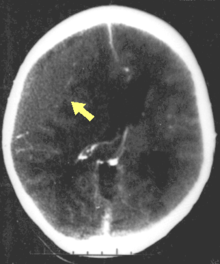

| CT scan showing cerebral contusions, hemorrhage within the hemispheres, subdural hematoma, and skull fractures[1] | |